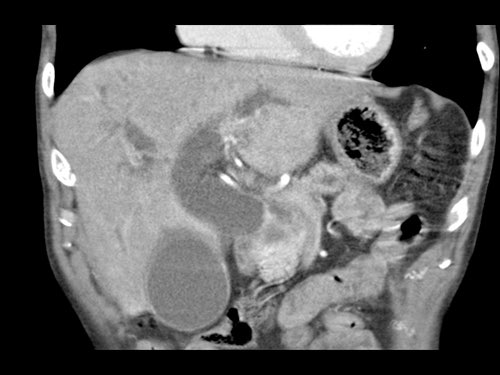

Ở những bệnh nhân dự kiến phẫu thuật tụy, điều quan trọng là cần đặc biệt chú ý tìm kiếm nguyên ủy bất thường của động mạch gan phải hoặc động mạch gan chung.

Các động mạch này xuất phát từ phía phải của động mạch mạc treo tràng trên (SMA) và đi qua vùng lân cận đầu tụy, làm tăng nguy cơ xâm lấn của khối u hoặc tổn thương do phẫu thuật.

Tần suất được ghi nhận của các bất thường đặc hiệu này lần lượt là 11-21% và 0,5-5%.

Sự liên quan mạch máu được đánh giá rõ hơn trên ảnh tái tạo mặt phẳng đứng dọc. Có sự áp sát 90 – 180° của động mạch gan phải thay thế (mũi tên trắng) bởi ung thư biểu mô tuyến đầu tụy (đầu mũi tên trắng).

Động mạch gan trái nguyên bản đi theo hướng ra trước hơn, tĩnh mạch cửa nằm ở giữa.

Cuộc phẫu thuật là cắt bỏ diện R1.